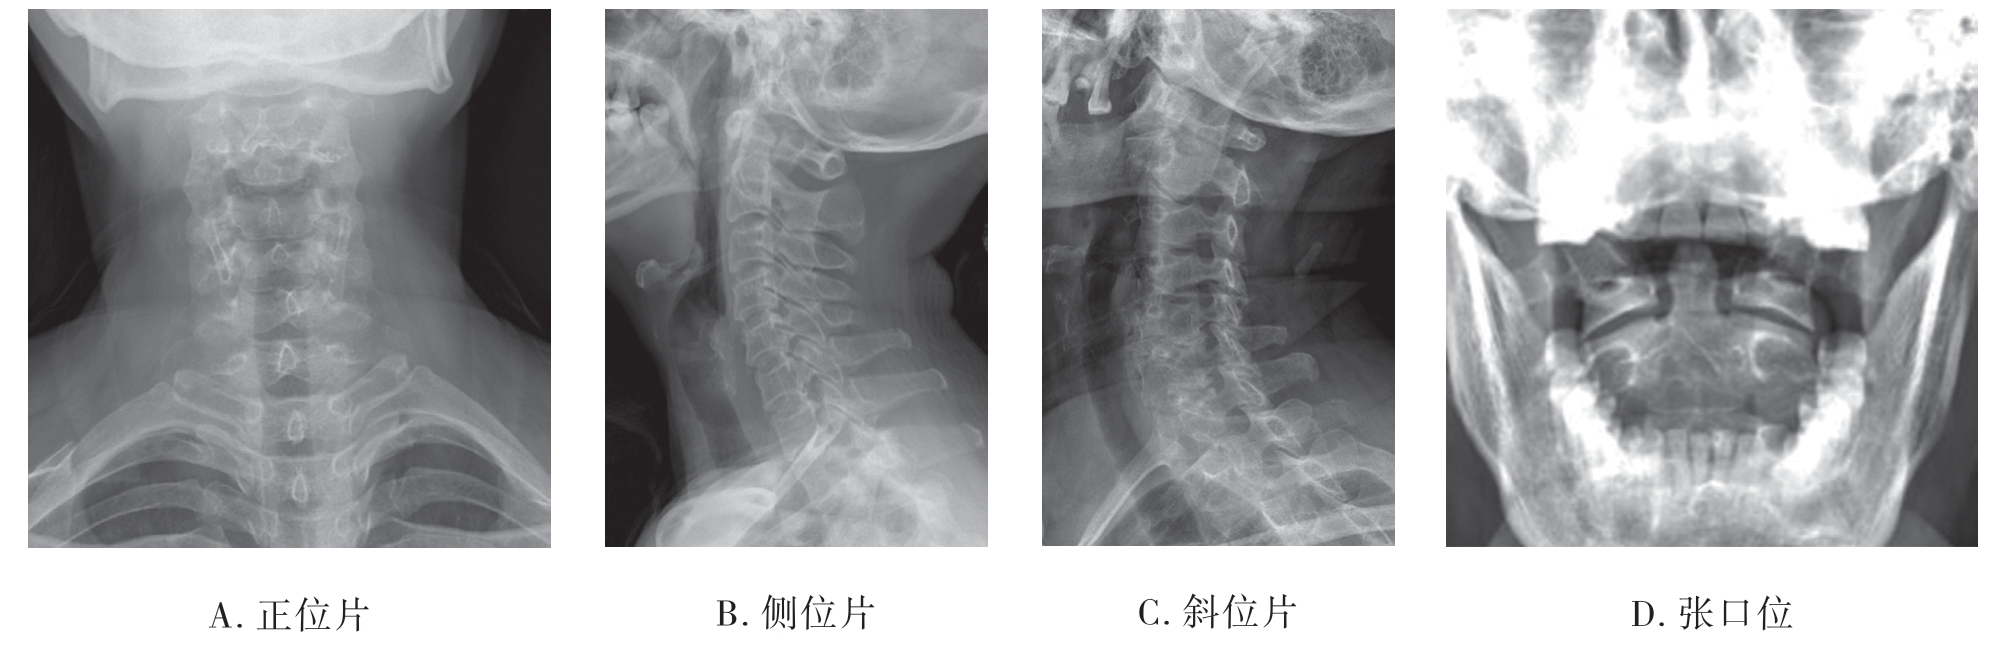

(1)颈椎X线片

1)正位X线片:可显示第3颈椎至第2胸椎的椎体、椎弓根、棘突、椎间隙、钩椎关节及其周围软组织(图7-2-2A)。

2)侧位X线片:可显示全部颈椎的椎体、椎间隙、小关节、棘突及周围软组织(图7-2-2B)。

3)斜位X线片:主要显示颈椎的椎间孔、椎弓根结构(图7-2-2C)。

4)张口位X线片:只有张口位才可显示寰椎的侧块、枢椎的齿状突及寰枢椎间关节突关节结构(图7-2-2D)。

图7-2-2 正常成人颈椎X线片